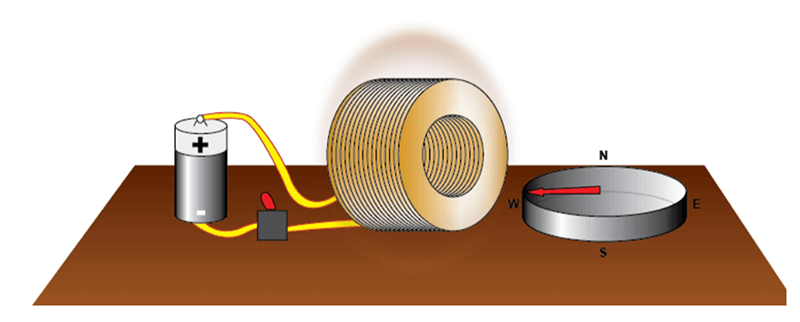

Two early 19th century discoveries ultimately led to the discovery of MRI late in the 20th century. Both of these discoveries are explained on the following slides. The experiment of Ørsted shows that a circulating current induces a magnetic field.

In 1820 after a long series of experiments, Ørsted discovered that a magnetized needle placed near a conductor moved when the wires were connected to a battery. At the time, the notions of electric circuit and current were unknown, but Ørsted suspected a link between electricity and magnetism. This experiment was the inspiration for the invention of coils to generate a magnetic field. If we turn the switch on, electrical current can flow through the coil and create a magnetic field.

As we saw when explaining the experiment of Ørsted, a rotating current creates a magnetic field. This is the property used for this type of magnet. A coil created by winding copper wires produces a magnetic field when an electric current flows through it. The direction of the magnetic field will depend on the axis of the tunnel of the coil. The intensity of the magnetic field is proportional to the intensity of current passing through the coil.

Resistive magnets have a homogenous field. One of the advantages of this type of magnet is that it provides magnetic fields of good homogeneity that can be used in MRI. These magnets are used in all MRI machines to generate gradients. Resistive magnet, like permanent magnets, have a weak field. Also, electric consumption by resistive magnets is very high. This is why they are generally not used to create the principal field of a whole-body MRI beyond 0.5 T. This type of magnet is nevertheless used in MRI to create magnetic field gradients.